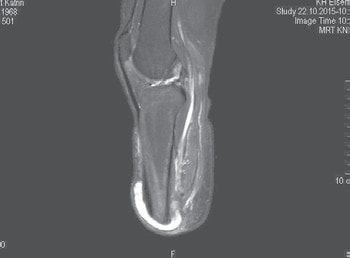

Um nicht zu viel Spannung auf die Muskulatur auszuüben, bedarf es des Vorstellungsvermögens des Operateurs über die natürliche Vorspannung, da intraoperativ kein Messgerät zum Messen der Vorspannung zur Verfügung steht. Dies ist durchaus ein Problem. Es bedarf dazu einiger operativer Erfahrung, was zur Folge hat, dass eine Amputation keine Anfängeroperation sein kann. Die unter physiologischer Vorspannung stehende Muskulatur wird mit dünnen Fäden der Stärke 00 am Periost bzw. Muskel zu Muskel befestigt. Dabei bleiben auch bei sorgfältiger Nahttechnik zumindest kleine Zwischenräume, die zwar mit zwei Drainagen behandelt werden, aber trotzdem etwas Hämatom oder Serom beinhalten. Das bedeutet bei der großen Wundfläche einige Quadratzentimeter, die einer längeren Heilungszeit (Konsolidierungszeit) nach Abschluss der oberflächlichen Narbenbildung bedürfen. Müller-Wohlfahrt et al. 8 haben ihre Erfolge bezüglich der relativ schnellen Muskelheilung nach Muskelfaserriss, Muskelbündelriss und totaler Muskelruptur anlässlich der 64. Jahrestagung der VSOU im Jahr 2016 so erklärt, dass das im Bereich des Risses vorhandene Hämatom/Serom punktiert werde und sich so die Rissenden wieder annähern und somit schneller verheilen könnten (Abb. 7, 8, 9a u. b).

Eine Heilung mit Hämatom/Serom benötigt demzufolge eine längere Zeit (Konsolidierungszeit). Solange diese nicht vollständig abgeschlossen ist, ist der Stumpf bei unnötiger Belastung durch das Abreißen der Muskulatur gefährdet (Abb. 6a). Müller-Wohlfahrt et al. geben folgende Heilungszeiten bei Sportlern an: